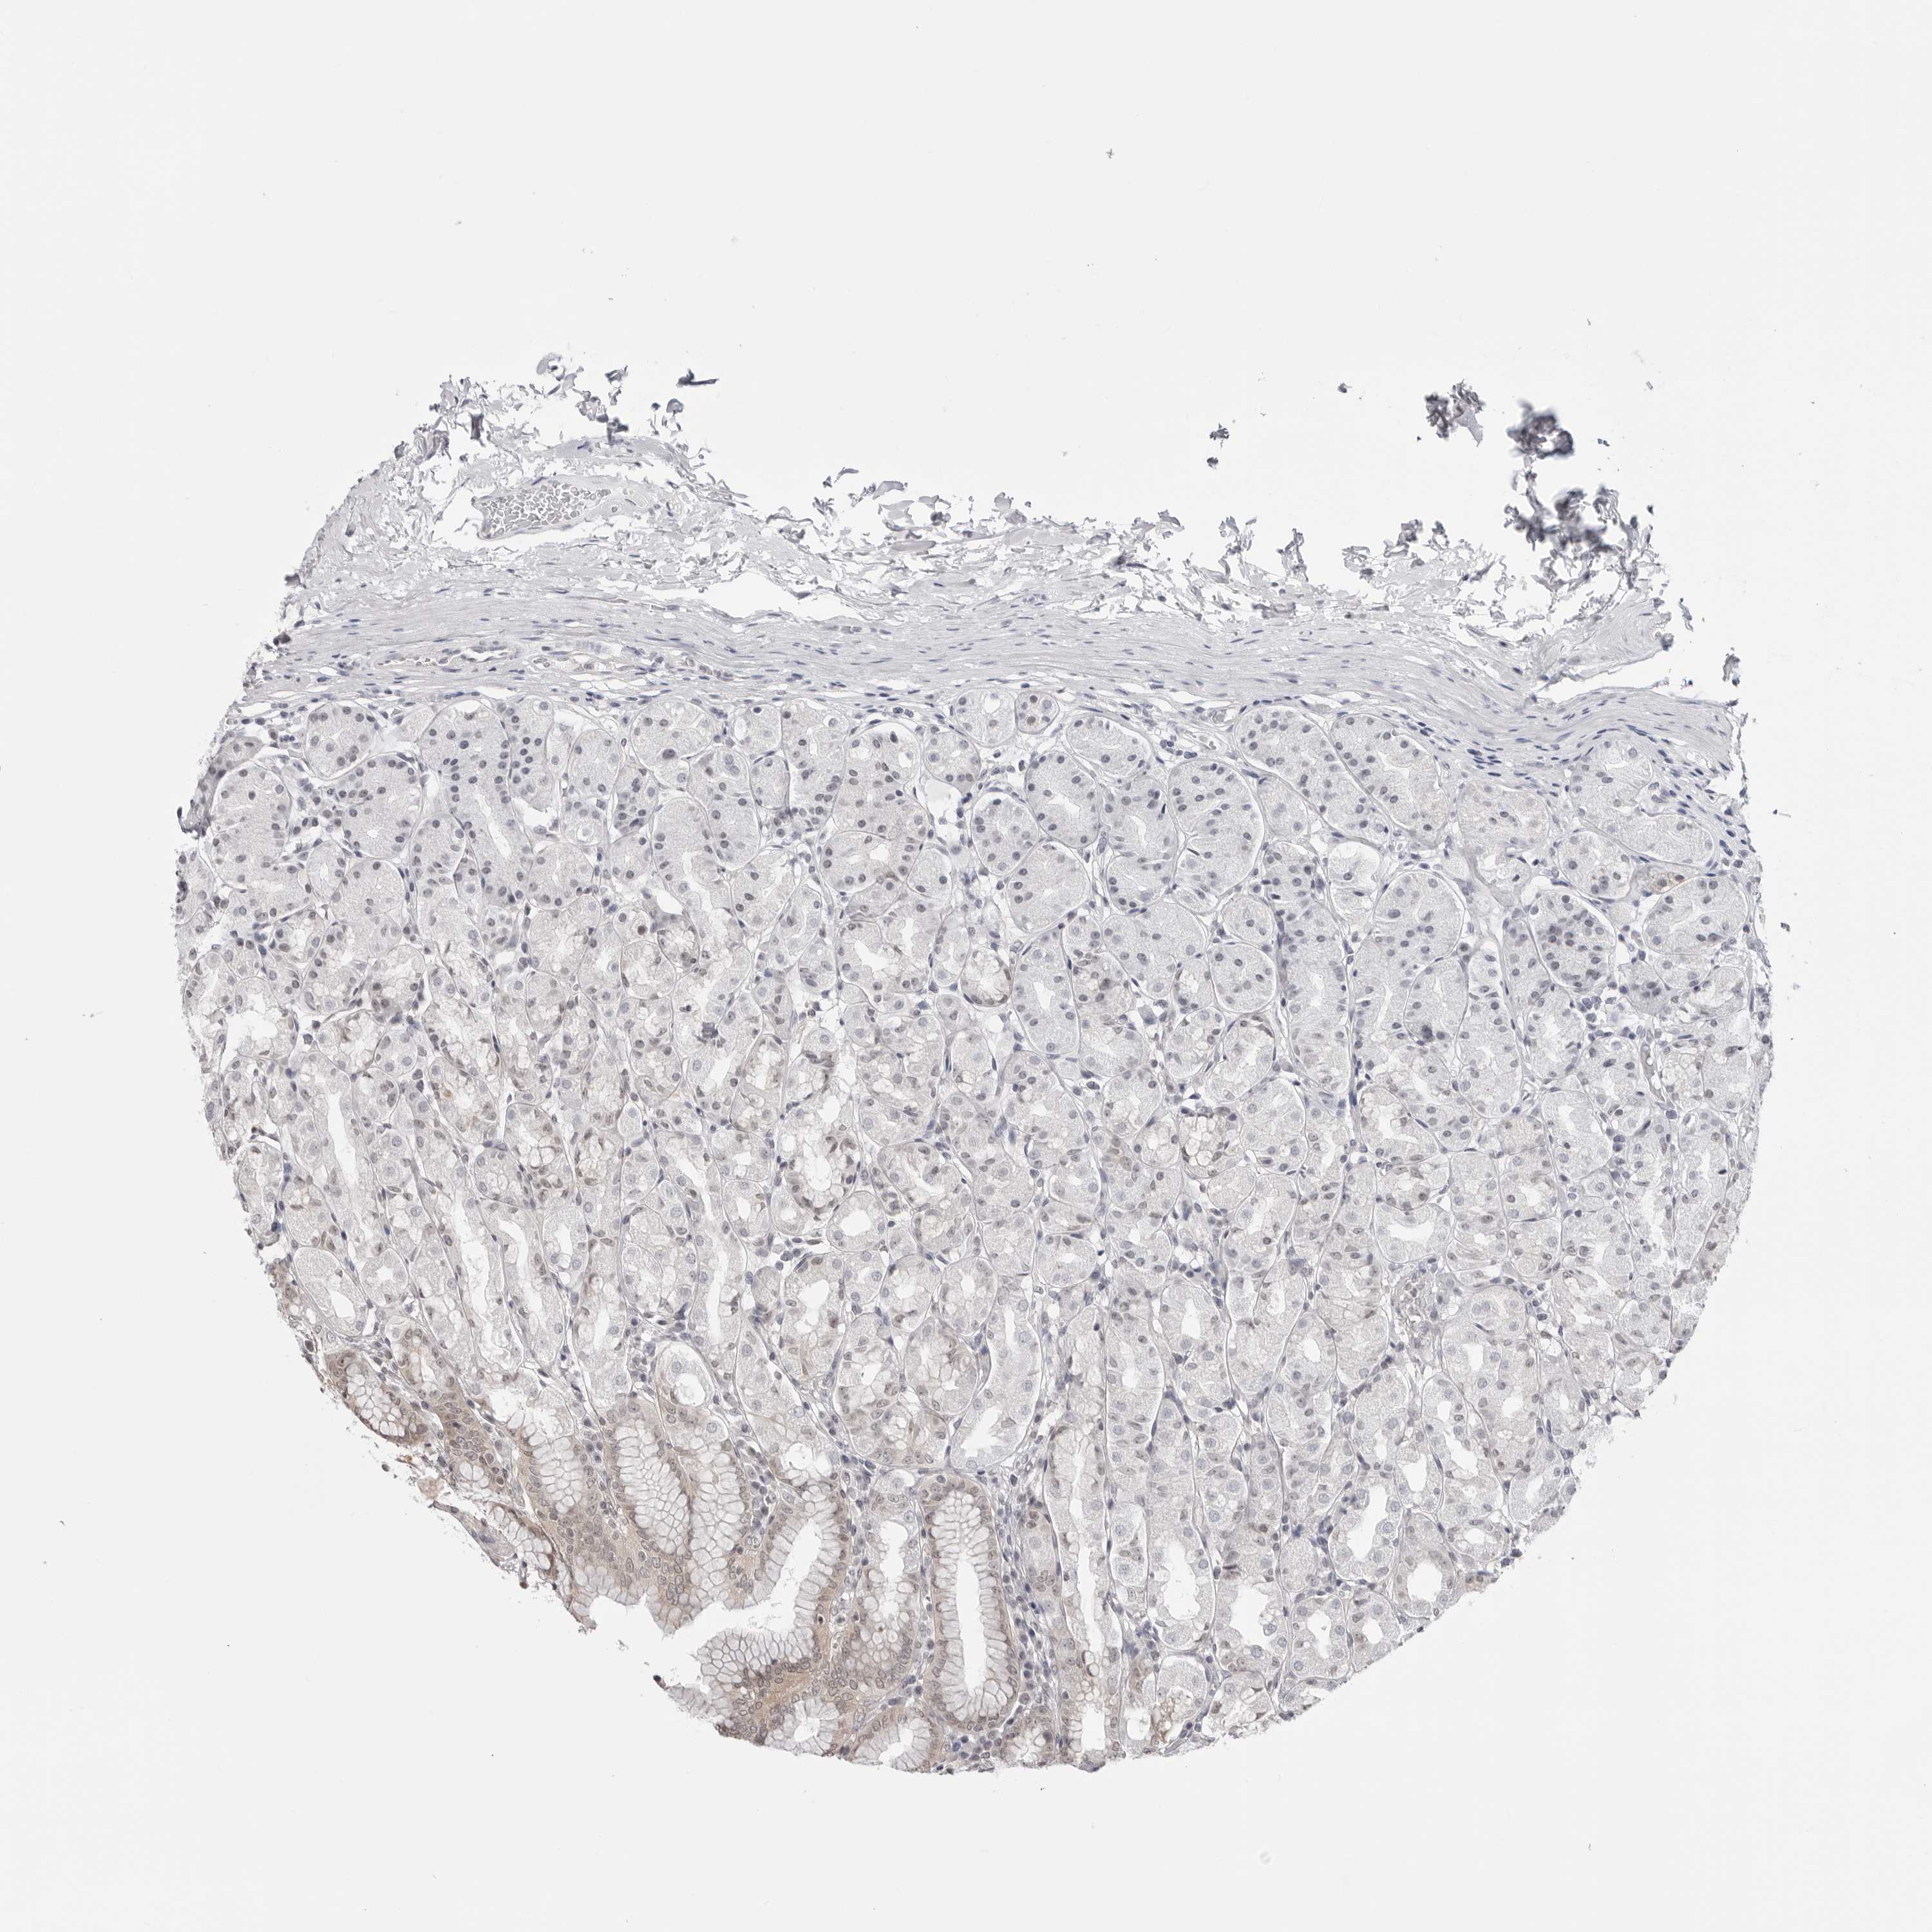

STOMACH 1 - Antibody stainingi

Antibody staining in the annotated cell types in the current human tissue is reported as not detected, low, medium, or high, based on conventional immunohistochemistry profiling in selected tissues. This score is based on the combination of the staining intensity and fraction of stained cells.

Each image is clickable and will lead to virtual microscopy that enables deeper exploration of all samples and also displays staining intensity scores, fraction scores and subcellular localization as well as patient and tissue information for each sample.

Antibody HPA026918Antibody CAB013274Antibody CAB018389

Glandular cells LowMediumMedium